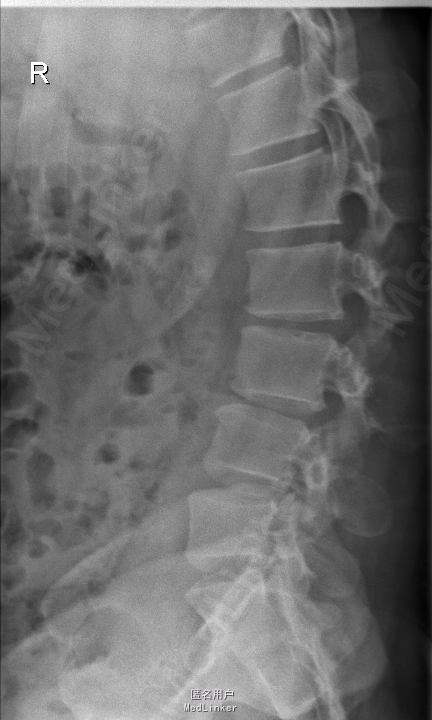

查体:腰部叩痛,腰部活动受限,左侧膝内侧、小腿外侧、内踝、足部感觉减退,右侧小腿、足背感觉减退,屈髋、伸膝、踝背伸肌肌力左侧4级,右侧4-5级,踇背伸、跖屈肌肌力左侧3-4级,右侧4级,双侧膝腱反射+,跟腱反射+,双侧巴氏征阴性,直腿抬高试验左侧40°阳性,右侧阴性。 辅助检查: X-ray:腰椎退行性变,多节段不稳 CT:腰椎间盘突出并椎管狭窄伴钙化,腰2-3,3-4,4-5,腰5骶1 MR:腰椎间盘突出并椎管狭窄,腰2-3,3-4,4-5,腰5骶1 上传受限无法全部上传,见谅

诊断:腰椎间盘突出症并椎管狭窄 处理: 1、完善相关辅助检查,明确诊断,有无手术指证; 2、完善手术评估,有无手术禁忌,手术风险及并发症; 3、在全麻下行腰椎后路多节段减压椎间植骨融合内固定术 4、腰2-3,腰3-4行开窗减压,腰4-5,腰5-骶1行椎间Cage植骨融合

随访: 1、应常规术后1个月、3个月、半年随访; 2、术后患者腰痛较前减轻,下肢麻木感觉较前好转,下肢活动较前有力,屈髋、伸膝、踝背伸肌肌力左侧4级,右侧4-5级,踇背伸、跖屈肌力左侧4级+,右侧4-5级,左侧肢体抬高试验阴性。 讨论: 1、多节段腰椎间盘突出,手术指证把握 2、责任节段的确立,以影像学间盘突出节段为依据,以影像学与临床表现确立责任节段间盘为依据,还是术中探查为金标准? 3、多节段间盘突出,开窗髓核VS椎间植骨融合? 4、开窗髓核与椎间植骨融合相结合,如何确定融合节段与开窗节段? 5、多节段内固定,腰椎活动度影响,稳定与腰椎活动功能的平衡?